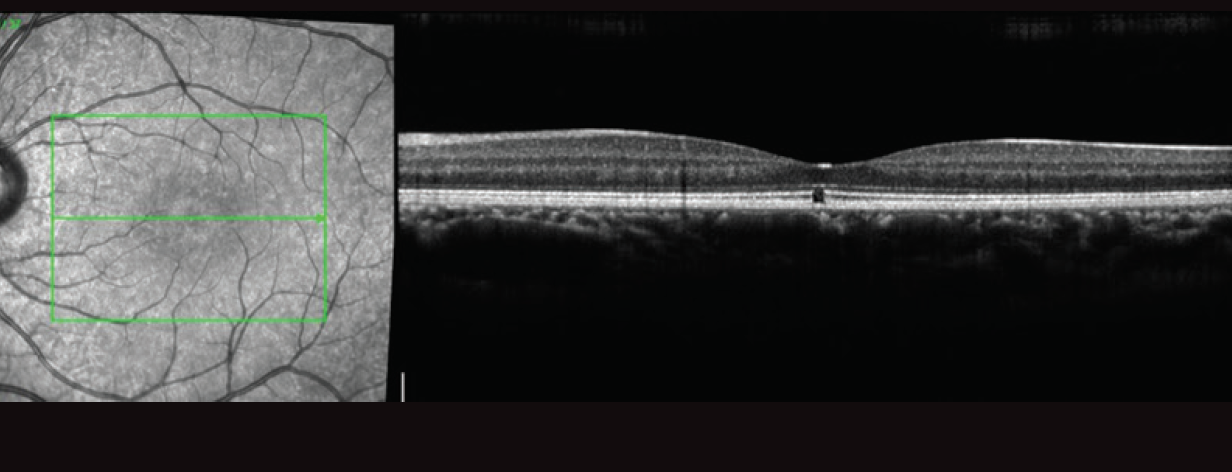

Baseline visual acuity before this presentation was 20/25 in each eye (OU). At this visit, her visual acuity OS had decreased to 20/400. Anterior segment examination was notable for an absence of inflammation. Funduscopic exam OD revealed focal hypopigmentation at the fovea (Figure 2A), and spectral-domain optical coherence tomography (OCT) demonstrated a focal defect involving the outer retina and ellipsoid layer, which was stable from 3 years prior (Figure 3). Fundoscopic exam OS was notable for absence of any posterior segment inflammation and a circumscribed central granular yellow lesion (Figure 2B). OCT revealed disruption of the subfoveal ellipsoid layer, hyperreflective debris involving the outer retina and apical surface of the retinal pigment epithelium (RPE), and a thickened choroid OS (Figure 4). Fluorescein angiography (FA) OS demonstrated early central hypofluorescence and parafoveal patchy hyperfluorescence without leakage (Figure 5). Electroretinography (ERG) demonstrated normal amplitudes OD and reduction of macular sensitivity OS.

Figure 4. OCT reveals disruption of the subfoveal ellipsoid layer OS and hyperreflective debris on the apical surface of the RPE.

The case described here demonstrates classic OCT findings seen in UAIM, with heterogeneous hyperreflective thickening at the level of the outer retina and RPE resulting in disruption of the ellipsoid layer.3,4 On OCT at follow-up, the outer retinal layers were restored, which corresponded with visual recovery.